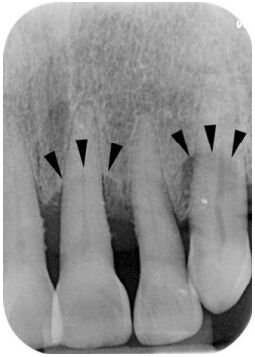

69.附圖中,所標示的牙周炎齒槽突(alveolar process)變化,最可能為何?

(A)頰側或舌側皮質板喪失(buccal or lingual cortical plate loss) (B)根叉侵犯(furcation involvement) (C)齒間陷口(interdental crater) (D)水平骨缺損(horizontal bone loss)